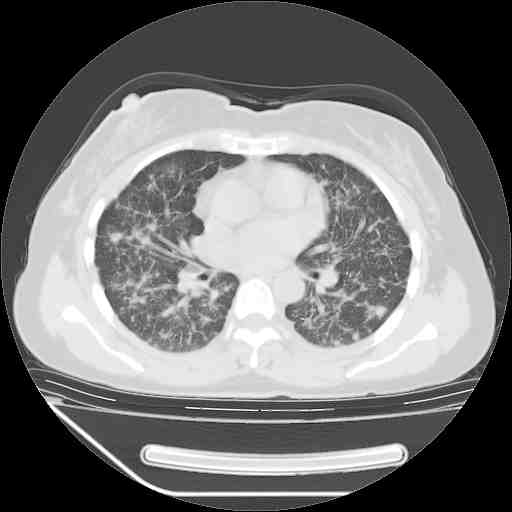

下面是今天刚刚做的,在上海治疗,吃了家属也说不清的一种药,一个月1万左右,

考虑  腺癌肺内转移,治疗较前病灶缩小、减少

支持肺癌并肺内淋巴管炎,  原发灶小了,但转移较前片明显了.

支持右肺下叶周围型肺癌并肺内淋巴管炎,  原发灶小了,但转移较前片明显了.。

标准的细支气管肺泡癌呀!治疗后病情有所控制,也没治愈的迹象!

标准的癌性淋巴管炎!!距大去之日不远已.

应该是比较典型的细支气管炎,4个月的时间不说明问题;有时候疾病是有个相对稳定期的,如果喝10元一斤的茶叶估计也会这样。